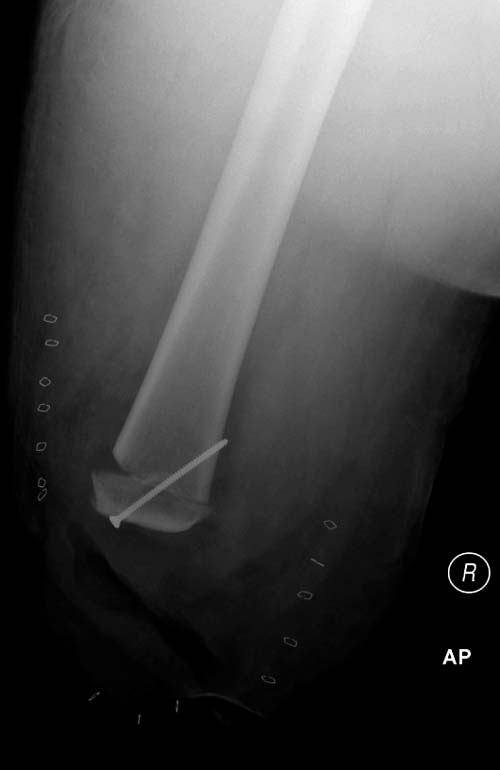

Здесь снимки, которые показывают направление стержня, а также идею

репозиции вытяжением. На рентгенопроницаемых столах имеется возможность

установить дополнительную раму, где по желанию можно увеличить или

уменьшить высоту угла вытяжения. Для репозиции таза больной в положение

на спине, стержень для вытяжения остается во время операции. Система

подойдет для тракции головки бедра из вертлужной впадины, и для этого

стерильная веревка и Synthes Universal Chuck with T-Handle.